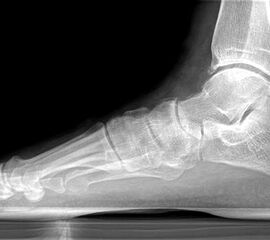

Abbildung Nr. 1: Röntgen Fuß: dp und seitlich stehend.